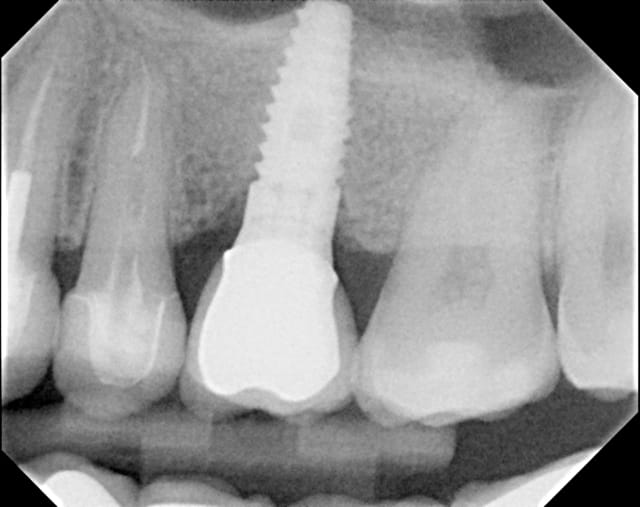

19/02/2012 à 22h20

Vous est-il arrivé de voir une résoption en apex d'un implant situé dans une greffe sinusale?

radiographie à suivre avec perte osseuse, merci

Implant juillet 2010 cnmkmg - Eugenol

Couronne  lors de la mise en bouche stvmce - Eugenol

flicflac

11/03/2012 à 19h24

la radio viendra...

perte osseuse au site de greffe sinusal en apex des implants, çà vous est déjà arrivé?

06/04/2012 à 05h22

la voila

Post greffe sinusale pdsngu - Eugenol

Il me semble que ton implant est trop enfoui, la connection se trouve au niveau osseux, donc perte ossseuse automatique avec une connection hex de ce genre.

C'est bizarre, comme si l'os non stimulé s'était résorbé. (ce qui est la règle au final ^^)

Ceramik, je parle de perte osseuse à l'apex. Le laser lock a été enfouie de moitié, ce qui est recommandé, regarde plus haut la BW à la mise en bouche. Pas de perte à ce niveau, si tu le penses trop enfouie, c'est que de l'os s'est formé en quantité non négligable, ety non c'est l'axe de la PA. PA=pas bon pour jugé du niveau osseux au collet.

Dans les cas de sinus lift non unitaire, j'utilise au plafond (greffon juxta membrane) de l'hydroxyapatite non résorbable et le reste de l'allogreffe.